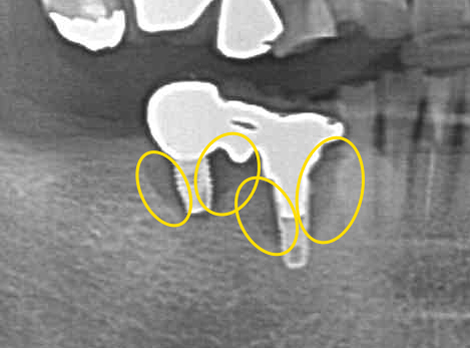

こちらは、先述のセカンドオピニオン来院時のレントゲン写真を拡大した写真です。

インプラントの周りが、少し色が変わっています。骨吸収が起きてしまっています。これは骨が溶けてなくなってしまっている状態です。

インプラントを支えている骨が無くなってしまっているので、インプラントがグラグラしてしまいます。このまま放置すると、更に骨が無くなっていき、ついにインプラントが抜け落ちてしまうことが予想されます。